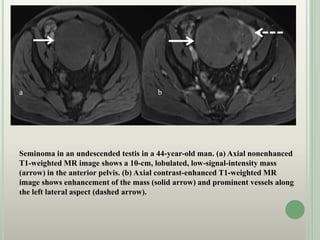

Seminoma in an undescended testis in a 44-year-old man. (a) Axial nonenhanced

T1-weighted MR image shows a 10-cm, lobulated, low-signal-intensity mass

(arrow) in the anterior pelvis. (b) Axial contrast-enhanced T1-weighted MR

image shows enhancement of the mass (solid arrow) and prominent vessels along

the left lateral aspect (dashed arrow).